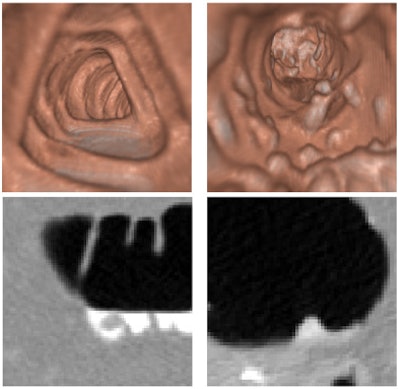

| With laxative colon preparation (left), residual materials tend to appear only in fluid form. Fecal tagging may be used to reveal polyps covered by the residual fluid (bottom left). With nonlaxative preparation (right), fecal tagging must be used to identify residual materials that tend to appear in solid form and imitate polypoid shapes (bottom right). All images courtesy of Dr. Hiro Yoshida. |